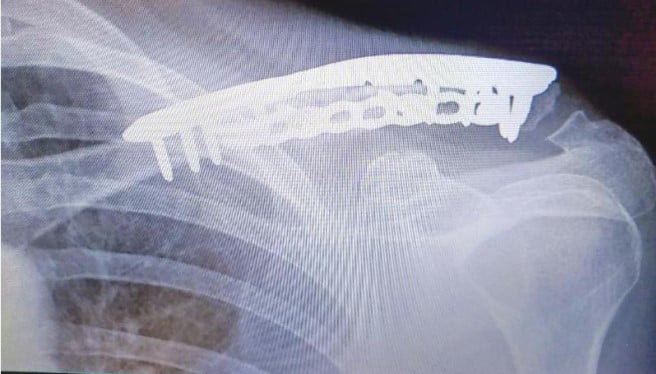

Following a major car accident in February 2024 that left me with multiple injuries (broken wrist, collar bone, and sternum), Dr. Sama led me through a challenging recovery that included several complex surgeries, the last of which took place in December 2025.